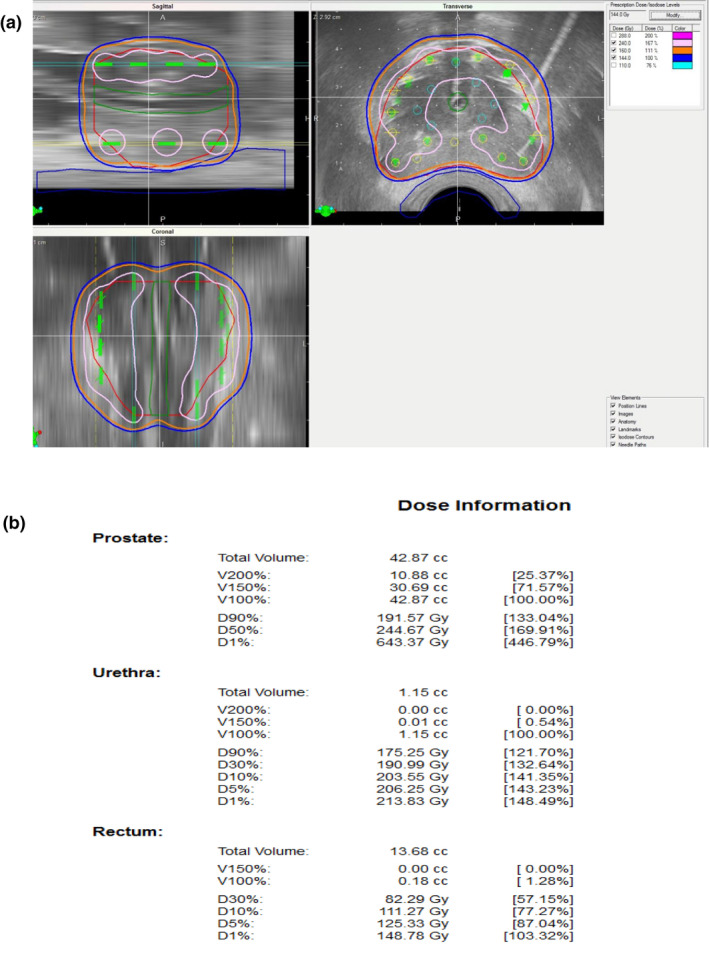

【 Step ⑩ 】As the final step, we check the entire dose distribution for all 2D views (sagittal, transverse, coronal) and confirm that the entire prostate target is covered with 160 Gy [Fig. 10(a)].

Fig. 10.

Final step: confirmation of dosimetry. (a): As the final step, check the entire dose distribution for all 2D views and confirm that the entire prostate target is covered with 160 Gy (orange). Note that the high‐dose band (240 Gy, pink) does not invade the urethra and rectum C (b): Confirm parameters including OAR.

Note that the high‐dose cloud (240 Gy) does not invade the urethra and rectum.

D90 should be over 190 Gy and V100 should be over 99%. Upon OAR parameters, UD30 should be under 215 Gy and R100 should be under 0.5cm3 [Fig. 10(b)].